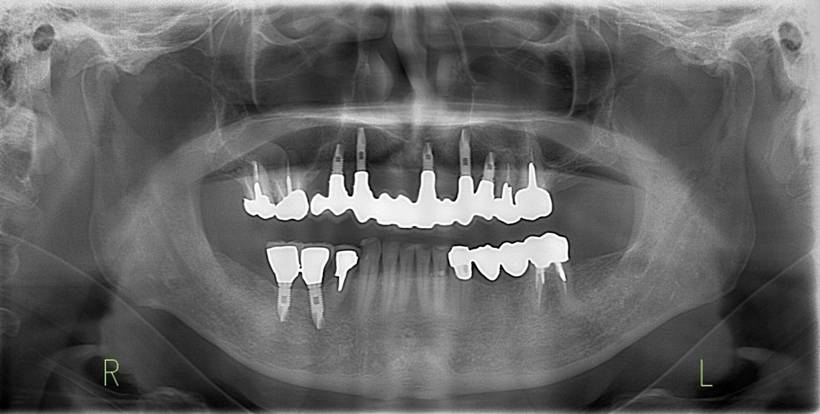

インプラント装着後6年。順調に経過しています。12か月毎のメインテナンスをしています。

上部構造装着後6年。ハイブリッドレジンを使用したため、少し艶がなくなってきました。上部構造の材料には金属、ハイブリッドレジン、セラミックなどがあります。セラミックはきれいですが欠けやすいため、最近はフルジルコニアを使っています。

上顎 少しすり減ってきました。

下顎。12か月に一度メインテナンスをしています。